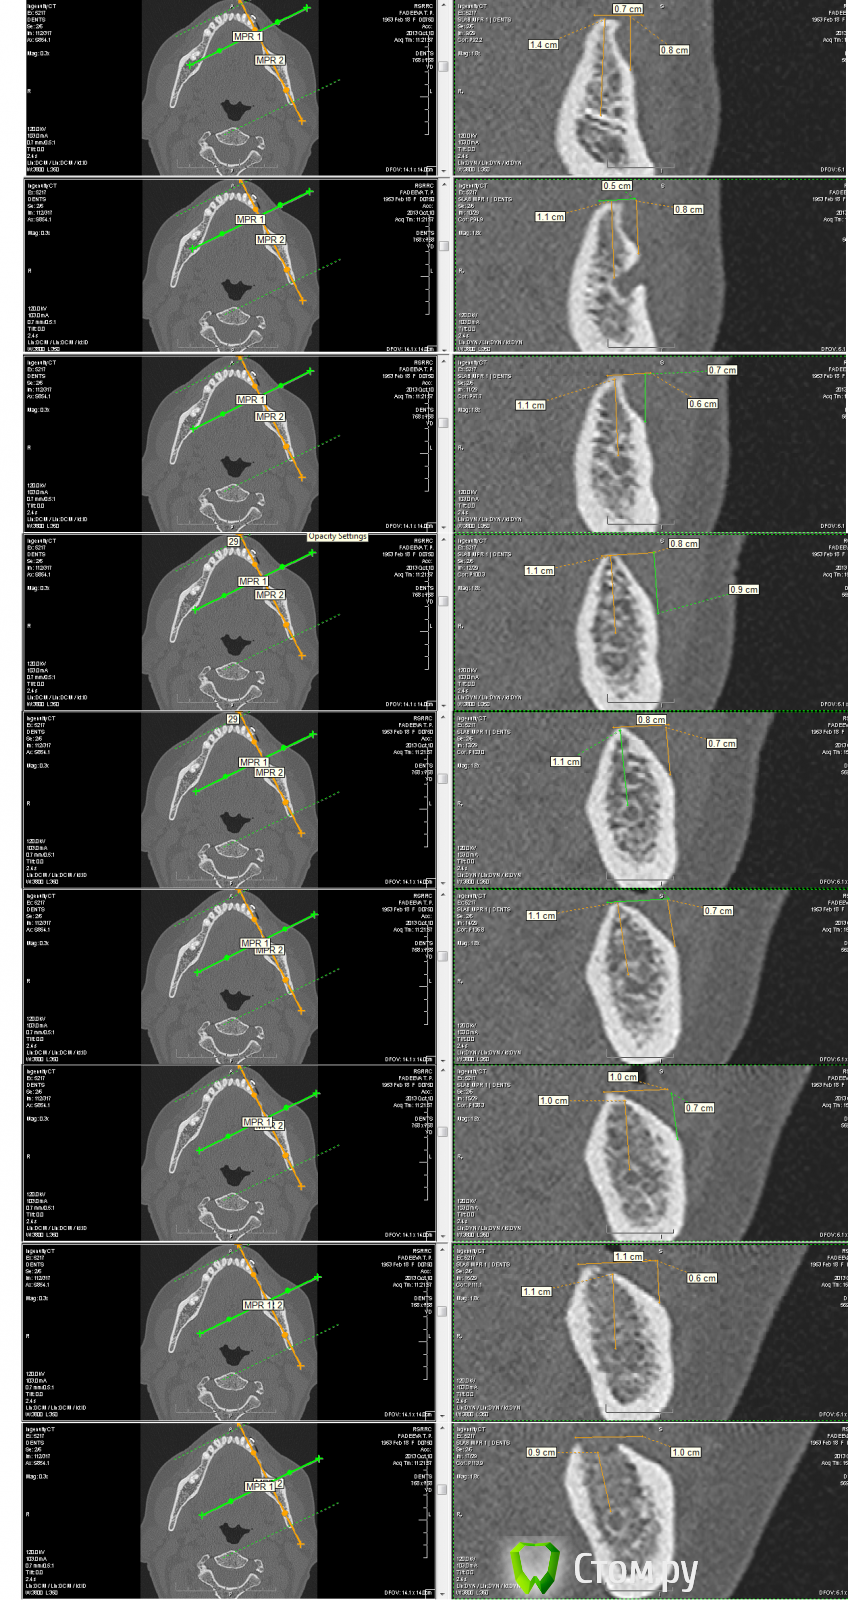

fmn Опубликовано 29 мая, 2014 Автор Поделиться Опубликовано 29 мая, 2014 Здесь пациентка - возрастная и с сопутствующими соматическими проблемами. Анестезиолога в клинике нет. Моей задачей было сделать хирургию максимально быстро и атравматично. В итоге, я выбрал компромиссный способ - пластику ксеногенным итальянским блоком. Блок укрывал мембраной эволюшн. Если честно, рассчитывал на более скромный результат. http://dispotrade-spb.ru/d/73725/d/osteobiol_dual_block.jpg 11 Ссылка на комментарий

fmn Опубликовано 29 мая, 2014 Автор Поделиться Опубликовано 29 мая, 2014 Фотопротокола не было, т.к. он съедает до 30% времени операции, а там время было критично. Исходная ситуация крупнее - в приложении. Ссылка на комментарий

fmn Опубликовано 29 мая, 2014 Автор Поделиться Опубликовано 29 мая, 2014 (изменено) О как! Красиво получилось! А по подробнее когда? Спасибо!В принципе, я уже всё написал. если интересует что-то ещё - спрашивайте. Хирургия была банальная: Замачивание блока. Разрез как на фото с имплантацией, отслойка, перфорация кортикалки, моделировка блока. Прикручивание винтами. Манипуляционно, блок после замачивания очень мягкий - напоминает губку для мытья посуды по консистенции, с жёстким кортикальным слоем. При фиксации возникает соблазн его немного "додавить", из-за чего он может доформироваться. Укрытие мембраной. Фиксация мембраны швами. Мобилизация лоскута, ушивание - так же как на фото. 3 дня был довольно резкий послеоперационный отёк, температура - но, в принципе, так же как и после аутокостной пластики. Изменено 29 мая, 2014 пользователем fmn Ссылка на комментарий

fmn Опубликовано 29 мая, 2014 Автор Поделиться Опубликовано 29 мая, 2014 (изменено) Через какое время открыли блок? Были ли какие то проблемы с подобными блоками? Производитель рекомендует открывать через 8 месяцев. Я открыл через 6 с половиной. Если честно, это моя первая операция с такими блоками. Я всегда относился и до сих пор отношусь к алло и ксено блокам с большой настороженностью. Здесь это был именно компромиссный вариант. Результаты меня приятно удивили и я решил поделиться ими. Надеюсь, для кого-то это окажется полезным. Изменено 29 мая, 2014 пользователем fmn 2 Ссылка на комментарий

Alexey Doc Опубликовано 29 мая, 2014 Поделиться Опубликовано 29 мая, 2014 Интересная работа с отличным результатом! Каковы были исходные размеры блока и каков прирост получили, качество костной ткани?Удобно ли было работать с блоком? 1 Ссылка на комментарий

fmn Опубликовано 29 мая, 2014 Автор Поделиться Опубликовано 29 мая, 2014 Интересная работа с отличным результатом! Каковы были исходные размеры блока и каков прирост получили, качество костной ткани?Удобно ли было работать с блоком?Спасибо! Если посмотреть по винтам, то резорбция не больше полутора мм. Качество кости порадовало. D2 по плотности. Работать было удобно. Ссылка на комментарий